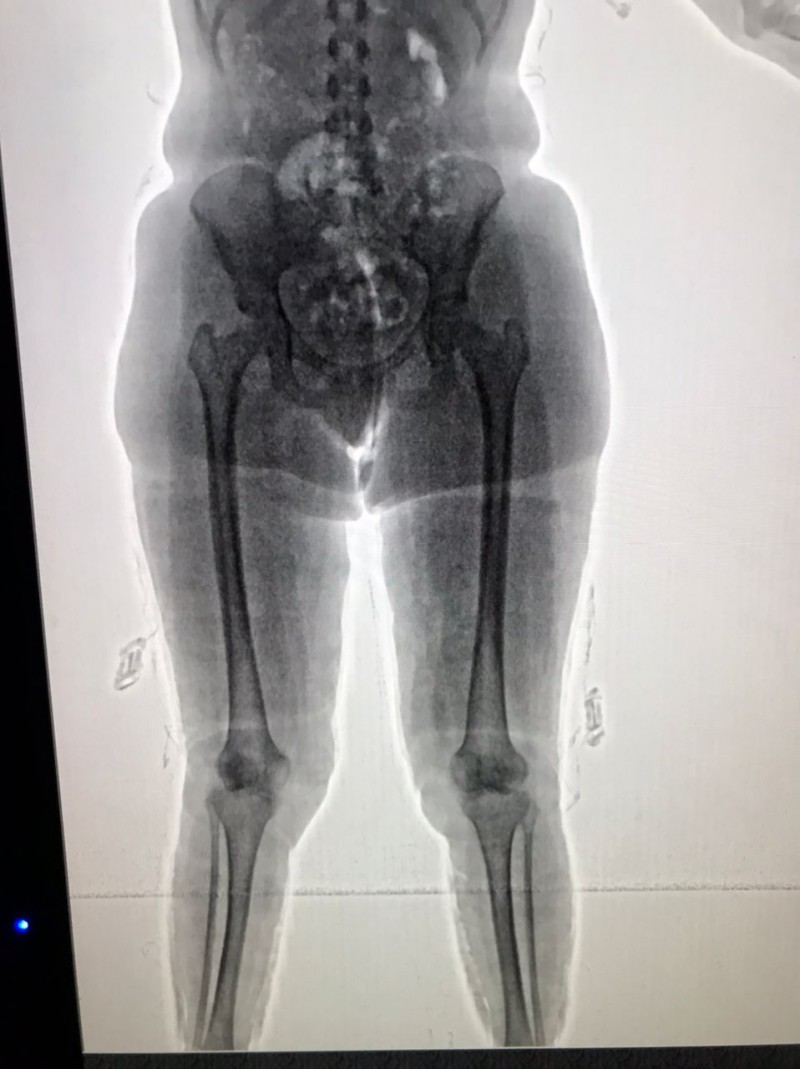

Por ocasião da fiscalização de rotina, mediante revista pessoal, a droga foi encontrada afixada no corpo dos paraguaios, oculta sob a roupa.